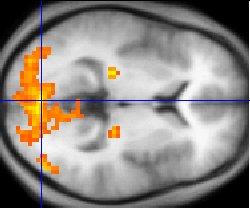

– Det er en populær oppfatning at de fargede områdene på bildene fra en hjernescanning er direkte bevis om hjerneaktivitet. Slik er det ikke, påpeker Fine.

Illustrasjonsfoto: wikimedia commons

Hun forklarer at fMri-maskinen ikke måler aktivitet i hjernecellene direkte, men måler hvilke deler av hjernen som får økt tilførsel av oksygenholdig blod. Under et eksperiment vil forskerne se hva som skjer i hjernen når forsøkspersonene utfører en bestemt oppgave, sammenlignet med hva som skjer i hviletilstand. Hvis det er mulig å observere en forskjell i hjerneaktiviteten, plasserer forskerne en fargeflekk på det aktuelle området på et bilde av hjernen.